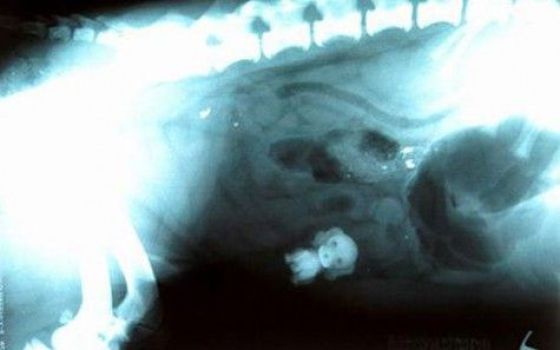

Dogs are awesome creatures, we don’t call them men’s best friends for no reason, but dogs are not always… smart. Some of them can eat things you could hardly think it is possible to swallow, I’m not talking about poo… no, I’m more thinking about items such as forks, soccer balls… and lots of other crazy things!